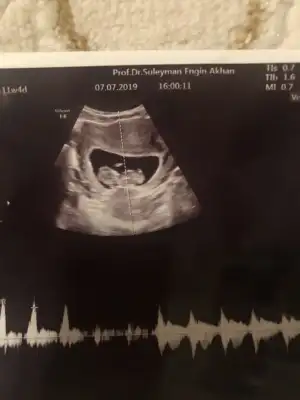

Nub yöntemine göre cinsiyet tahmini

15 haftadasınız dr yorum yapmadımı 11 yada 12 hafta olmalı nub için

Saglıkla gelsin bebeginiz inşallah daha önce sanki size tahminde bulunmuştum 11-12 haftalık usg nize erkek tahmini etmiştim nub teorisinde dimi